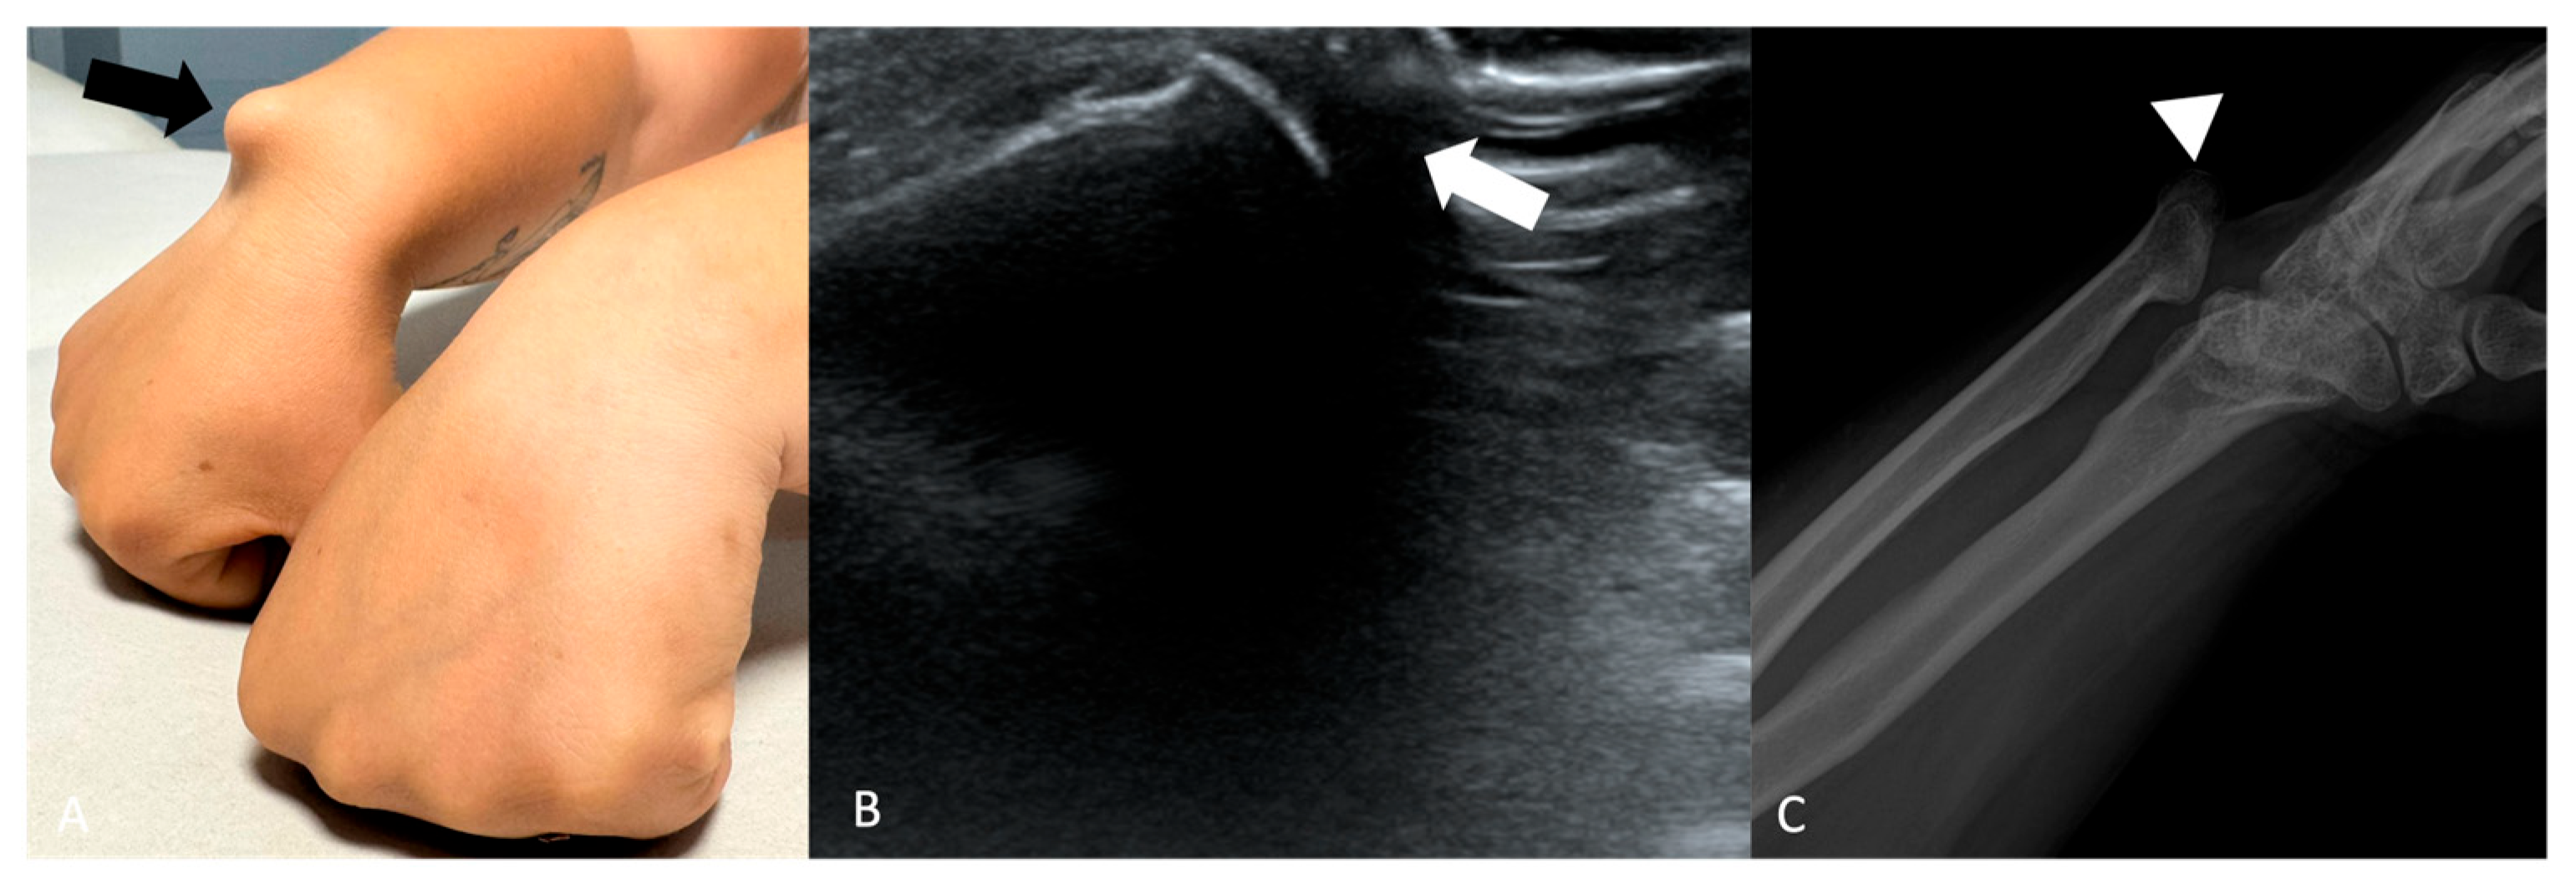

A typical cystic shoulder bump is the “geyser sign” (GS) (Figure 1), a characteristic imaging finding associated with chronic rotator cuff tears and degenerative changes in the acromioclavicular (AC) joint capsule. This sign is visualized as a fluid-filled collection above the AC joint, extending from the subacromial bursa through the compromised AC joint capsule into a subcutaneous space above the clavicle [16].

Figure 1.

(A) Elderly woman with a soft bump on the cranial portion of her right shoulder (black arrow). (B) coronal STIR and (C) sagittal T1-weighted showing a cystic lesion superior to the acromion-clavicular joint (white arrows). The lesion is raising subcutaneous soft tissue. Acromioclavicular osteoarthritis is noted (black arrowhead).